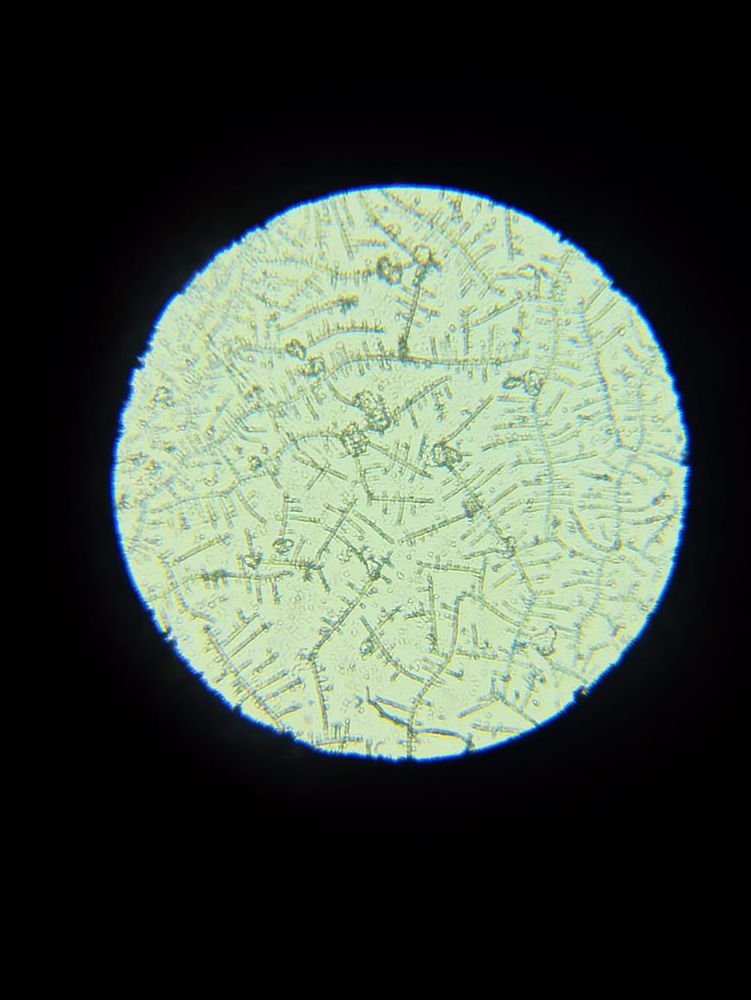

Я читала, что тесты на о показывают б. Возможно ли что и микроскоп на о, показал б.

Я уже ловила о в этом цикле, а по бт поймала из, ну как я думала, как тут вдруг. Вторая о или это первый признак б. Давайте попробуем разобраться. Подобного я р